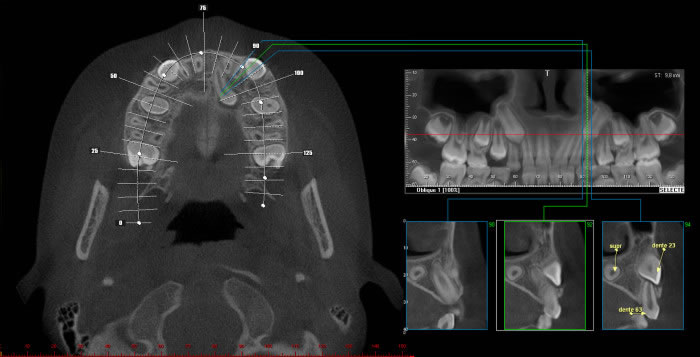

Caso2: Localização de dente retido

História clínica de exodontia do dente 38 há um ano, sem no entanto localizar o elemento dentário acreditando que o paciente havia engolido o dente. Na radiografia panorâmica observa-se a presença do dente 38 superposto ao ramo. Na tomografia localiza-se o dente no assoalho bucal.